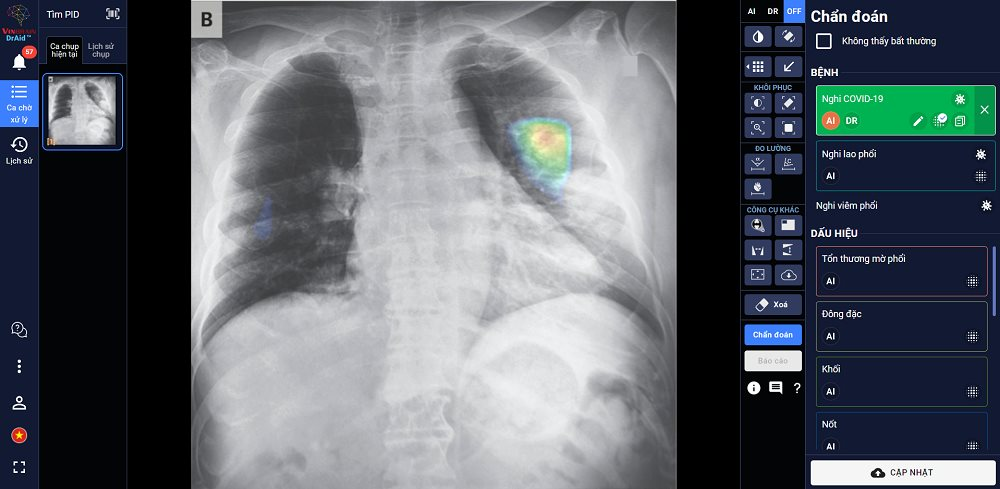

DrAid hiện có khả năng hỗ trợ chẩn đoán 20 dấu hiệu bất thường và bệnh lý về tim - phổi - xương với độ chính xác trên 88% trong vòng 5 giây, đồng thời tự động đưa ra báo cáo y tế theo chuẩn quốc tế JCI có khoanh vùng và đo kích thước chính xác tại khu vực bất thường.

Đặc biệt, DrAid™ mang lại 4 giá trị ưu việt trong phát hiện và điều trị Covid-19 dựa trên ảnh X-quang ngực thẳng gồm: Phát hiện nhanh góp phần sàng lọc mầm bệnh trong cộng đồng, song song cùng phương pháp xét nghiệm PCR.

Kết hợp cùng xét nghiệm PCR từ đó nâng cao độ chính xác, giảm thiểu tình trạng âm tính giả tránh bỏ sót; Hỗ trợ đánh giá tiên lượng tình trạng bệnh nhân thông qua lịch sử hình ảnh chụp X-quang, để từ đó có hướng điều trị phù hợp; Hỗ trợ tăng tính nhất quán và chuyển giao kiến thức của bác sĩ từ tuyến Trung ương tới cơ sở.

DrAid™ chẩn đoán và tiên lượng điều trị bệnh nhân Covid-19 dựa trên hình ảnh X-quang ngực thẳng